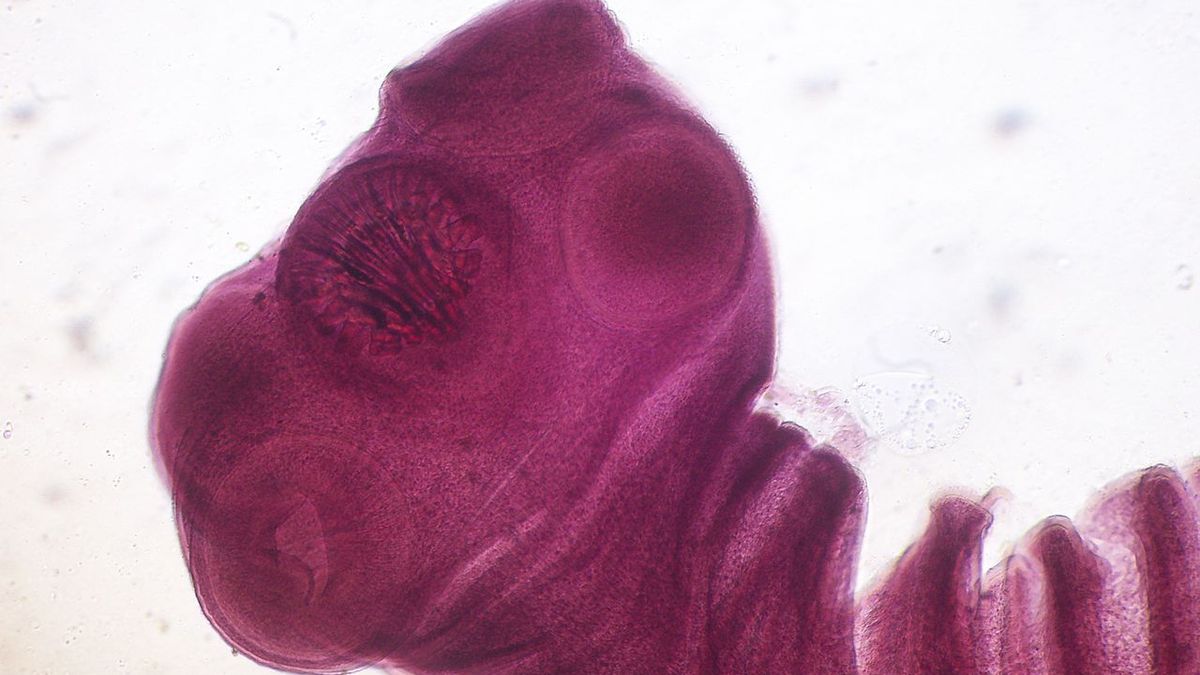

Tasemnice bezbranná (Taenia saginata). Detailně si obrázek můžete prohlédnout po rozkliknutí.

Tasemnice dlouhočlenná (Taenia solium)